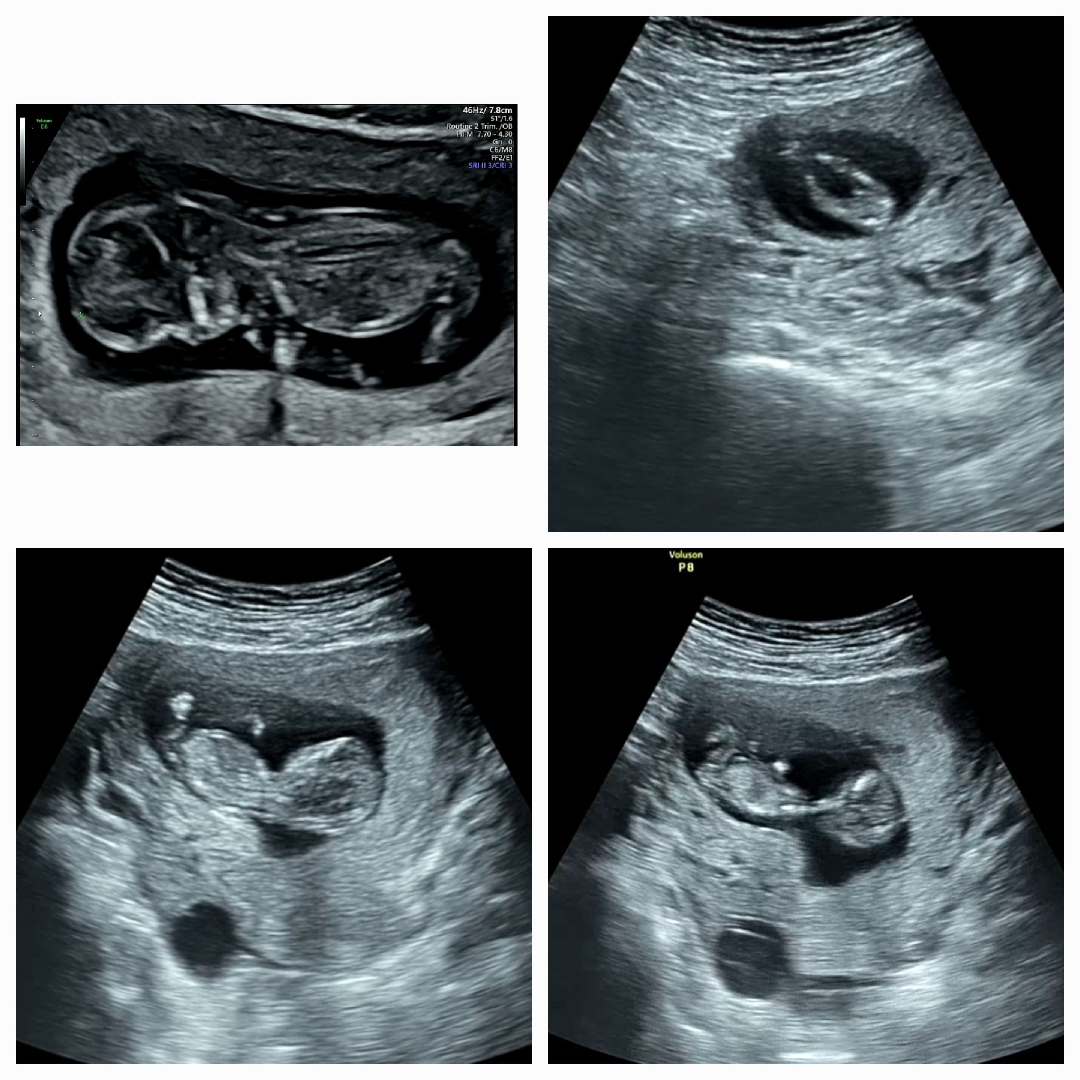

12주 각도법 고수님들 한번만 봐주세요~!!

고수님들 각도법 한번만 봐주세용~~